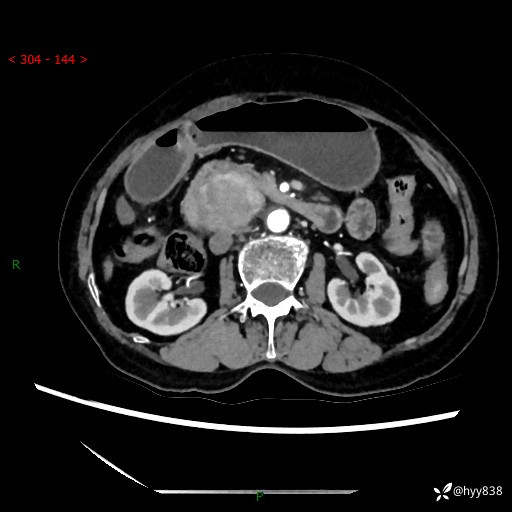

71岁/女,腹痛1月余。腹膜后肿物,间质瘤 VS 副节瘤 VS 平滑肌肉瘤---(有结果)

【患者信息】:71岁/女

【主诉】:腹痛1月余

【现病史及既往史】:患者于1月前无明显诱因出现右下腹部疼痛不适,呈阵发性隐痛,尚可耐受,放射至后背部及腰部疼痛,伴排便困难,不伴其它部位疼痛,无嗳气,无不洁饮食,无黑便,无恶心、呕吐、腹胀腹泻、呕血、发热、寒颤、厌油、黄疸,多次就诊于当地区太湖医院拍片示: 行抗炎等对症支持治疗,效果尚可。现患者上述不适症状明显进一步加重,为求进一步治疗遂来我院门诊就诊,门诊以“十二指肠肿瘤?”收住我科。 起病以来,精神、睡眠可,食欲可,大便异常、小便正常,体力、体重无明显下降。

【检查】:腹部CT增强扫描(外院CT平扫)